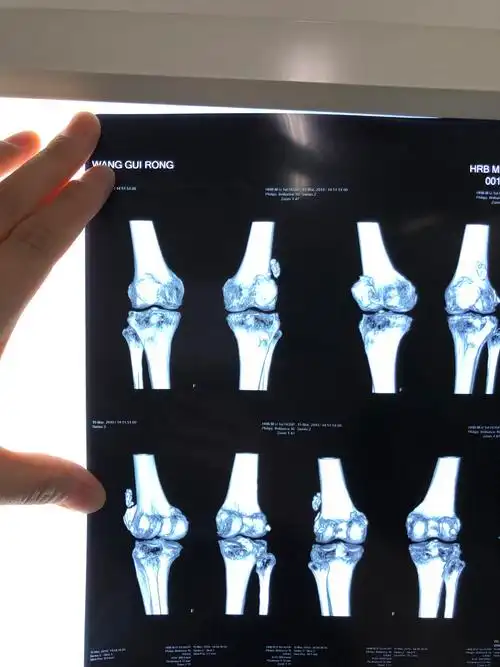

伸直就感觉里边硬邦邦的昨天在家附近医院拍的片子说考虑骨折,让做ct

各位高手请帮忙看下一张膝关节平片

膝关节后交叉止点撕脱性骨折

dr和ct可以清晰地显示骨质的形态及结构,可以判断是否存在骨质疏松